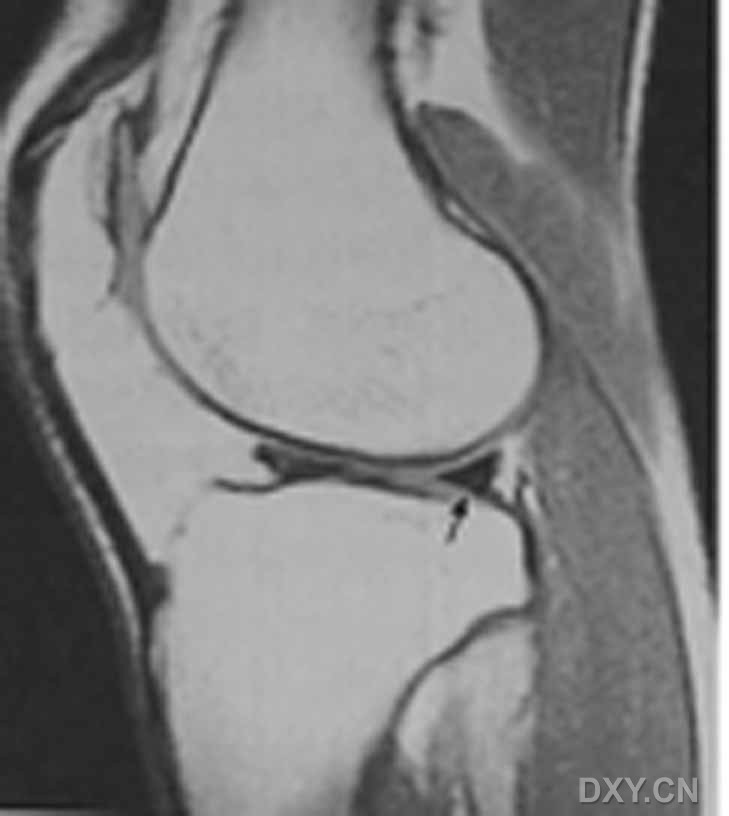

| III级 内侧半月板后角内见线形高信号达到半月板的关节面下缘

| 半月板斜行撕裂 斜行高信号影达半月板的下关节面缘 A:矢状T1 B:矢状T2